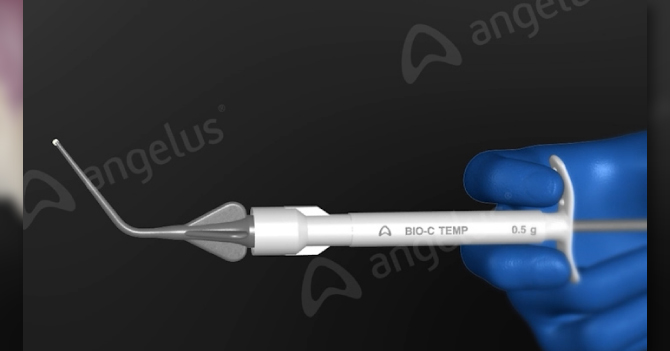

Ref 2832 - 1 jeringa de 0,5 g y 5 puntas aplicadoras

Ref 2833 - 4 jeringas de 0,5 g y 20 puntas aplicadoras